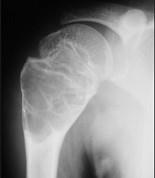

问题 男,15岁,右肩疼痛,请结合影像图像提出相应的诊断()

选项 A.嗜酸性肉芽肿 B.动脉瘤样骨性囊肿 C.骨样骨瘤 D.血管瘤 E.以上都不是

答案 B